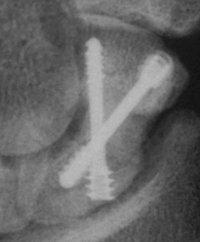

Clinical Example: Scaphoid fixation with more than one Herbert screw

A few years ago, I started putting in two Herbert screws for scaphoid fractures, with the thought that it would provide more rigid fixation. I think that it is helpful in some, but not all cases. Here are some of my results with a few variations...

Case 3. Another postop, better screw positioning.